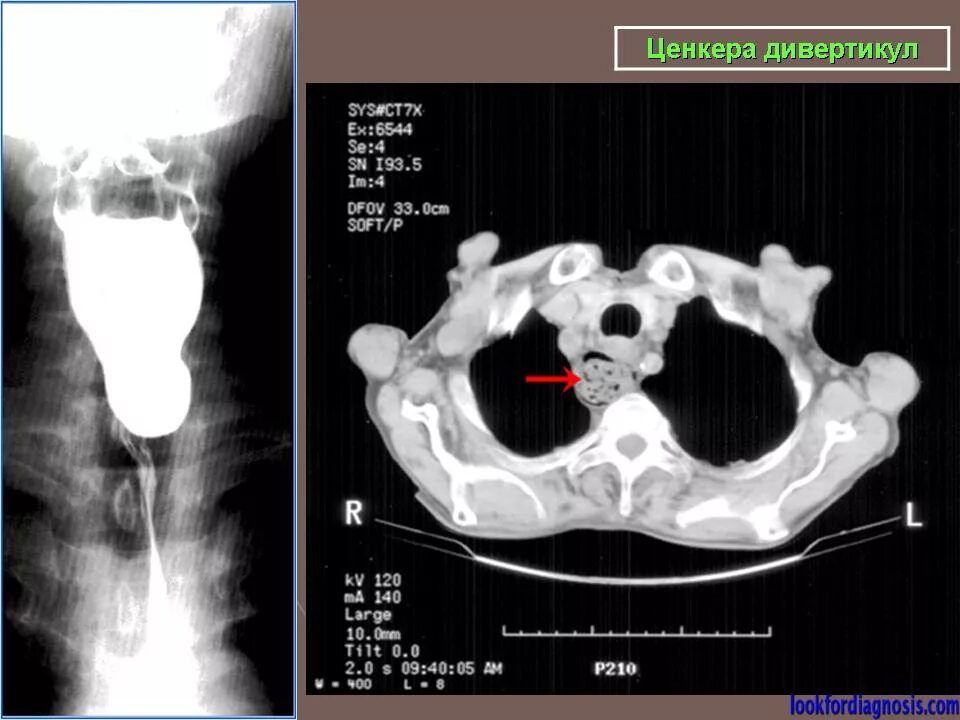

Дивертикул трахеи